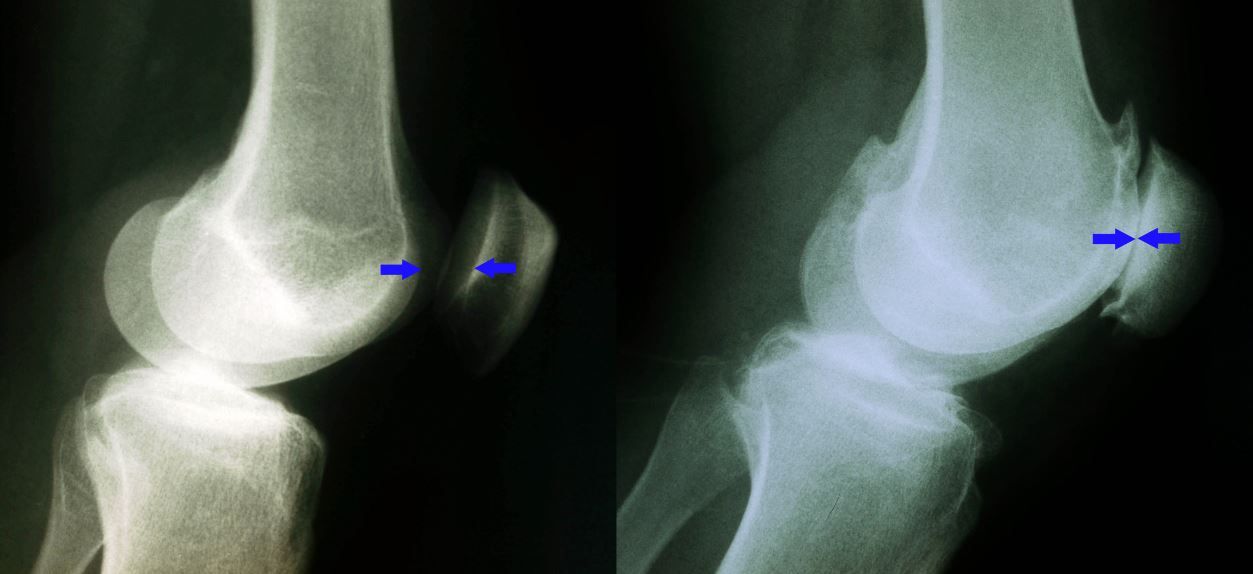

X-rays of a normal knee and an arthritic knee

(Left) This X-ray shows a normal knee from the side. The arrows point to the normal amount of space between the bones.

(Right) This X-ray shows narrowed joint space and bone rubbing on bone due to arthritis.

Images courtesy of Stuart J. Fischer, MD, FAAOS